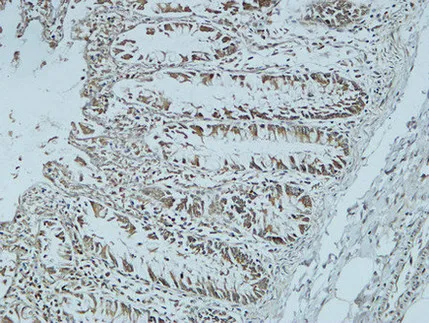

CD63 Rabbit Polyclonal Antibody

Cat: APRab08430

Size1:50μl Price1:$118

Size2:100μl Price2:$220

Size3:500μl Price3:$980

Size2:100μl Price2:$220

Size3:500μl Price3:$980